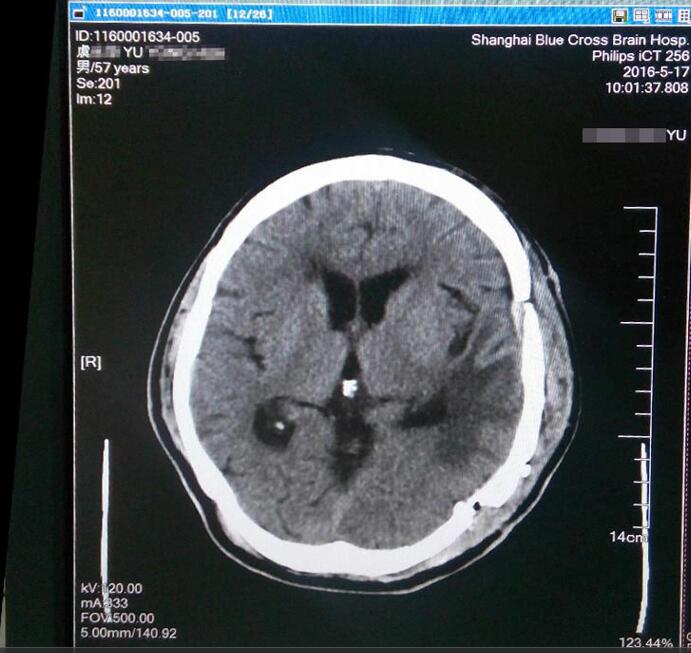

术后MRI显示肿瘤已消失